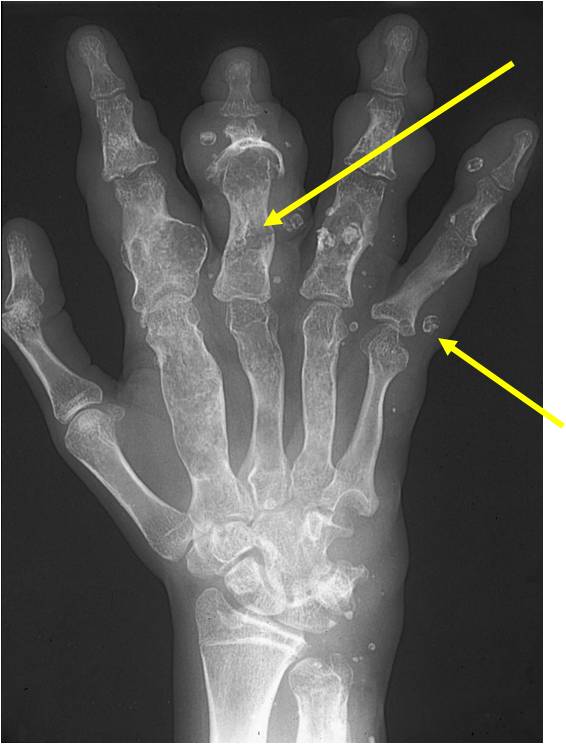

- Phleboliths (calcifications) usually seen in hemangiomas on X-ray

- Hands and feet greatest involvement

- Maffucci: Soft tissue mass/hemangiomas with phleboliths